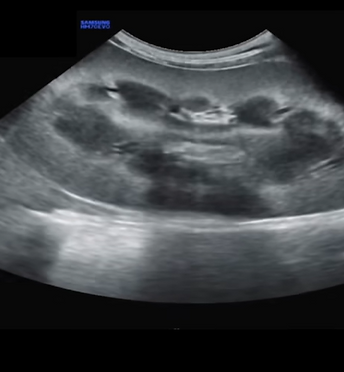

Ultrasound Scan Tips

Bite-size “how-to” videos for small animal ultrasound, made for busy clinic teams. From locating the pancreas to clean lymph node and adrenal views, each video shows positioning, probe moves and what to record - plus common pitfalls to avoid. Tap on an organ below to watch; follow us on YouTube for the full series.